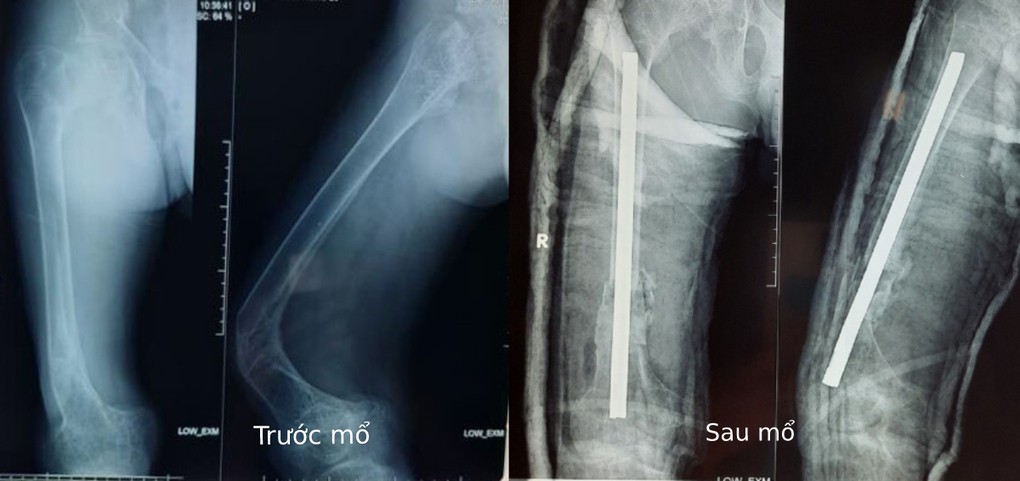

Bác sĩ chuyên khoa II Phan Văn Tiếp, khoa Chấn thương chỉnh hình, Bệnh viện đa khoa Xuyên Á, cho biết người bệnh vào cấp cứu ngày 10/10 trong tình trạng đùi phải gãy xương và biến dạng, đau đớn, không thể đi lại.

Bệnh nhân 20 tuổi song thân hình như một đứa trẻ 10 tuổi vì mắc bệnh xương thủy tinh, còn gọi là bệnh sinh xương bất toàn. Anh đã trải qua vô số lần gãy xương phải phẫu thuật, bó bột.

Bác sĩ Tiếp cho biết ca phẫu thuật cho bệnh nhân khá phức tạp vì xương đã gãy nhiều lần, lại rất mềm, cần thao tác nhẹ nhàng để các phần xương khác không vỡ vụn. Ê kip phẫu thuật đã cắt từng đoạn xương cong, biến dạng, khoan rộng ống tủy, xoay xếp ngược các xương sao cho thẳng trục rồi cố định bằng đinh Kuntscher. Bệnh nhân được ghép xương tự thân và khâu da từng lớp, sau cùng là nẹp bột đùi chân phải.

Hiện, 6 ngày sau mổ, sức khỏe người bệnh tương đối ổn định, vết thương đang phục hồi tốt. Anh sẽ tập vật lý trị liệu để đi lại và sinh hoạt bình thường.